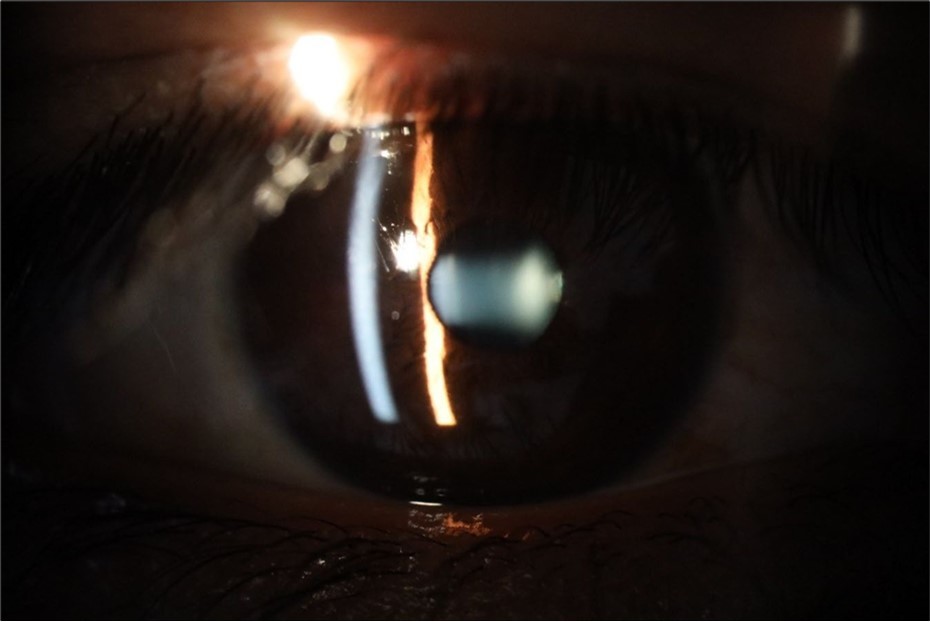

Figure 25.Mirror reflection of the affected eye (right side), with good appearance. This indicates that the transparent media of the eyeball (Cornea, anterior chamber, lens, and vitreous) are in good condition.

Figure 26.The macrograph of the anterior segment of the right eye (affected) shows very good transparency of the cornea, anterior chamber, lens, and vitreous.